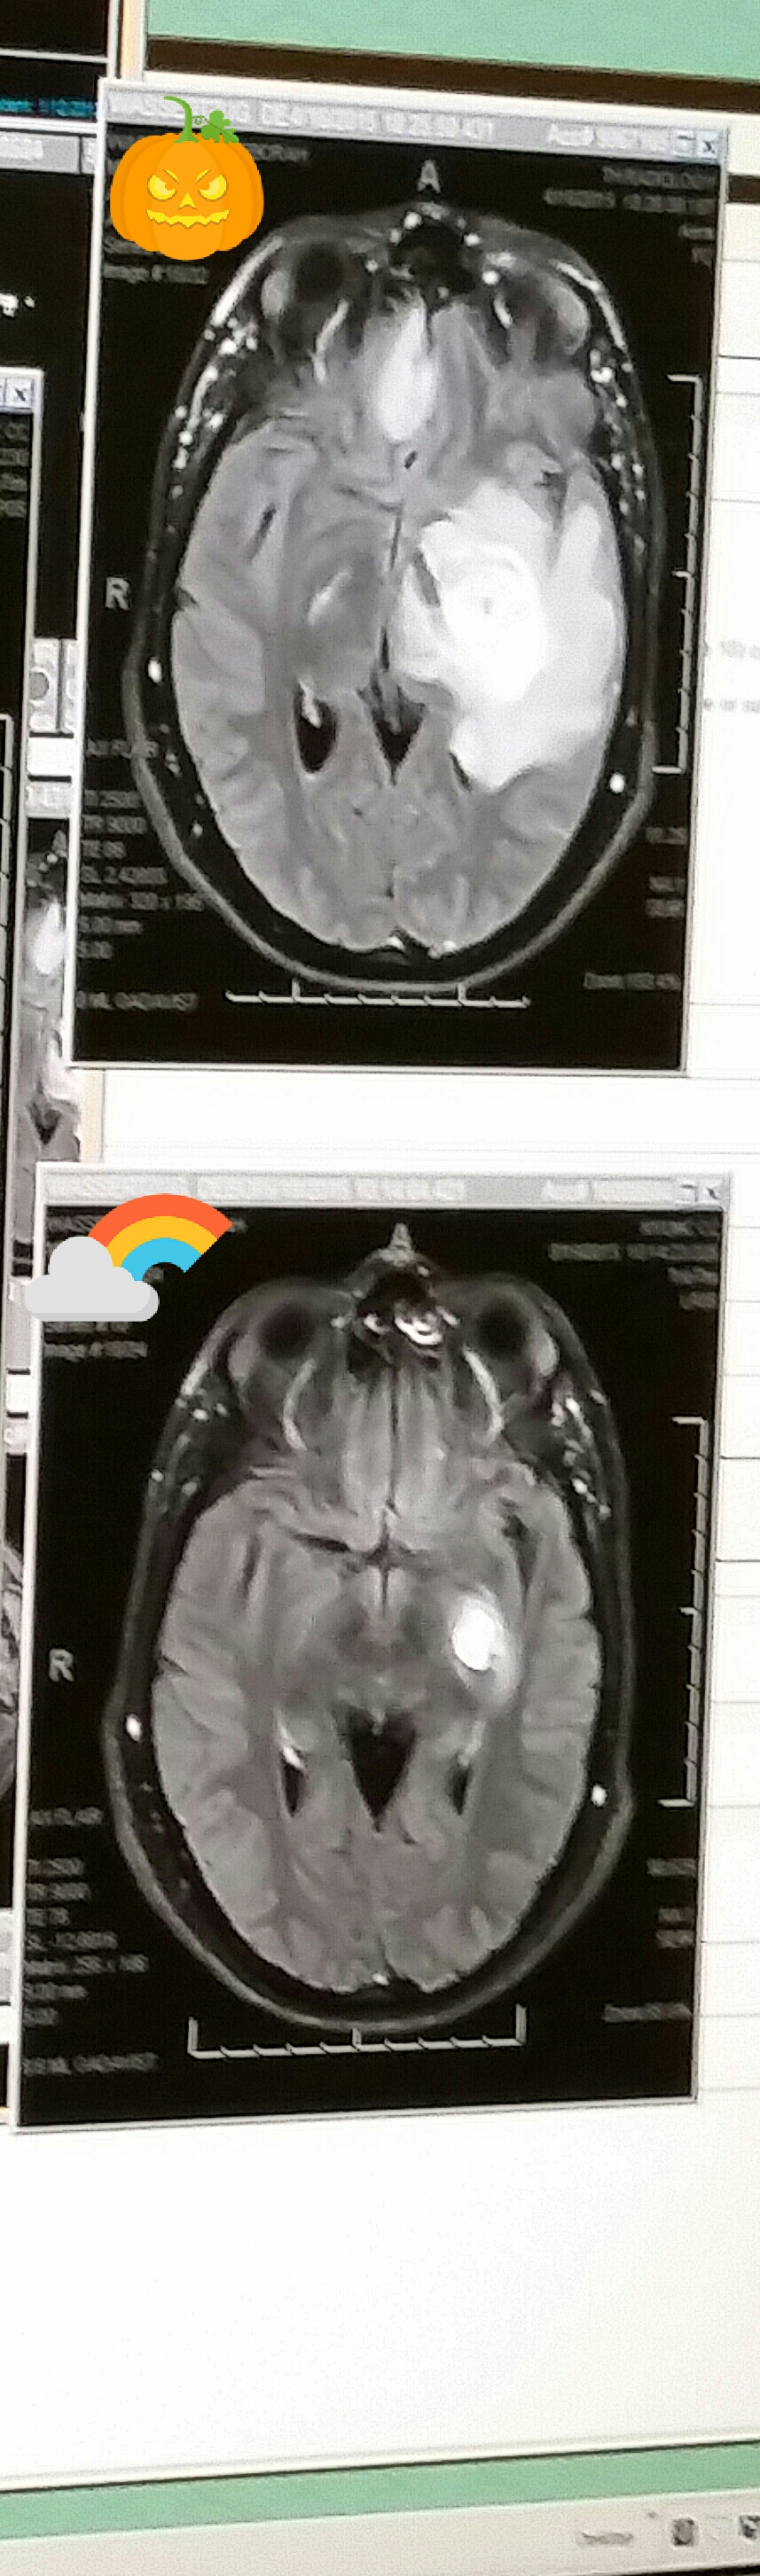

I did get up close and personal with my brain imagery today. Here’s what I saw:

image

Holy moly.

Looks like a bunch of x-rayed beetles, I know. Let’s zoom in.

The top image, the MRI from the ER, shows the area with the largest tumor, in mid-April. That’s the large white rose-like area. The bottom image shows the same area, last week. Notice a difference? Looks like something off The Weather Channel. I prefer the bottom forecast, don’t you?